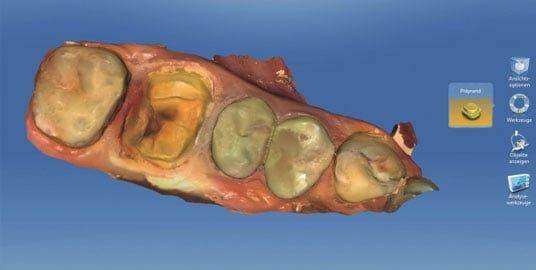

It is impressive to see the 3D model displayed in full color on the monitor. The various surfaces are shown in their natural shades. This direct and realistic feedback helps to distinguish between amalgam, gold or composite fillings and other subtle problems in the mouth.

3. We will now be able to see a high-resolution 3D representation of the area and start to design a new crown that will fit perfectly over the prepared tooth. Our patients often love getting to see us create a new tooth for them in real time, right there on the screen.